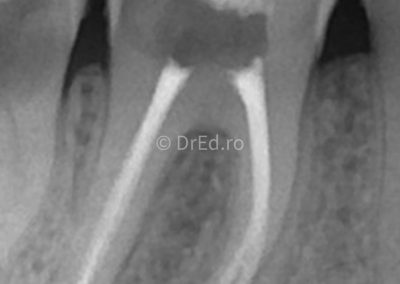

Galerie

Toate imaginile, fotografiile și radiografiile publicate pe acest site sunt protejate prin drepturi de autor și constituie proprietatea exclusivă a Dred.ro.

Aceste materiale sunt furnizate exclusiv în scop informativ și educațional și nu conțin date cu caracter personal sau informații care permit identificarea pacienților, în concordanță cu legislația privind protecția datelor cu caracter personal și GDPR.

Reproducerea, copierea, distribuirea, publicarea, transmiterea, modificarea sau orice altă utilizare, integrală ori parțială, a acestor materiale, în orice formă și prin orice mijloace, fără consimțământul prealabil scris al titularului drepturilor, este strict interzisă și poate atrage răspunderea civilă și/sau penală, în condițiile legii aplicabile privind drepturile de autor și protecția proprietății intelectuale.